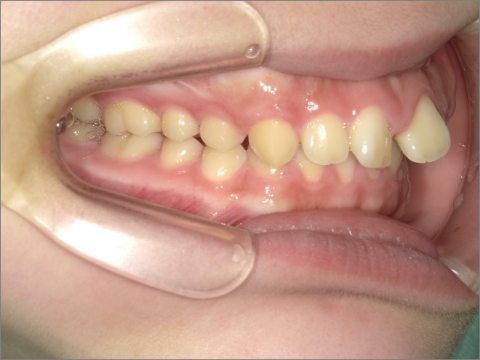

ご年齢 35歳男性 治療期間 2022/08/22〜2023/03/24(1年5ヶ月)

診断 110,000円(税込) アライナー 550,000円(税込) リテーナー 55,000円(税込)

ご年齢 35歳男性

治療期間 2022/08/22〜2023/03/24(1年5ヶ月)

診断 110,000円(税込)

アライナー 550,000円(税込)

リテーナー 55,000円(税込)

BEFORE

AFTER